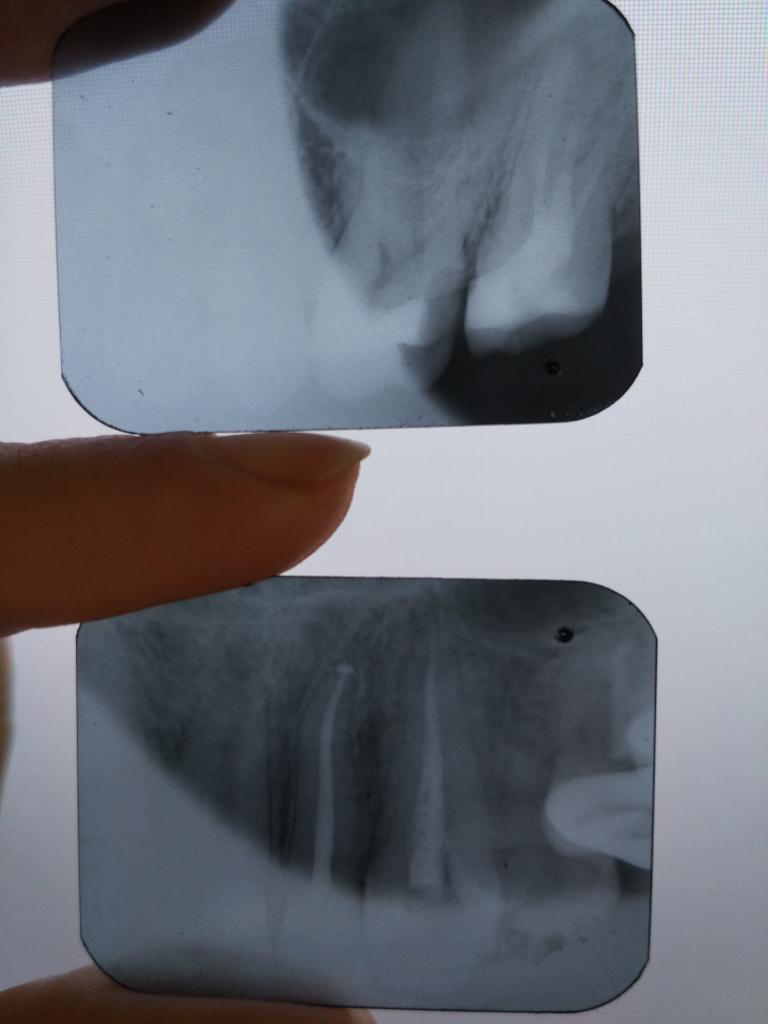

Лечила страшнючий периодонтит верхнего крайнего зуба, там был недолеченный пульпит четырехлетней давности.

Открыли зуб, оттуда вышло много гадости, на неделю ставили какое-то противное лекарство. Потом почистили и запломбировали каналы.

Прошел месяц, при накусывании на этот зуб во рту привкус того лекарства, со временем чуть меньше, но все равно жевать на ту сторону невозможно, до тошноты.

Снимки спустя месяц, если там что-то понятно...

Это после лечения на верхнем снимке седьмой зуб?

Спустя месяц после лечения оба снимка, 7й зуб

Привкус был сразу очень сильный, постепенно стал слабее, но все равно очень чувствуется.

Какие материалы использовались, не знаю, не спрашивала и не говорили.

Ну по поводу седьмого слов нет...

Что сейчас в шестом, который более к переди? Временная пломба? Субстанция там не ренгенконтрастная.

...мягко говоря, по снимку, пломбировка каналов выглядит не очень...

...а нижний снимок явно не семерки...

Да, сорри, нижний снимок двойки, по нему вопросов нет. Просто делала снимки в один день.

...качественная пломбировка у вас в двойке и тройке (нижний снимок)... не надо быть академиком, чтобы увидеть отличие качественно и некачественно запломбированного канала...